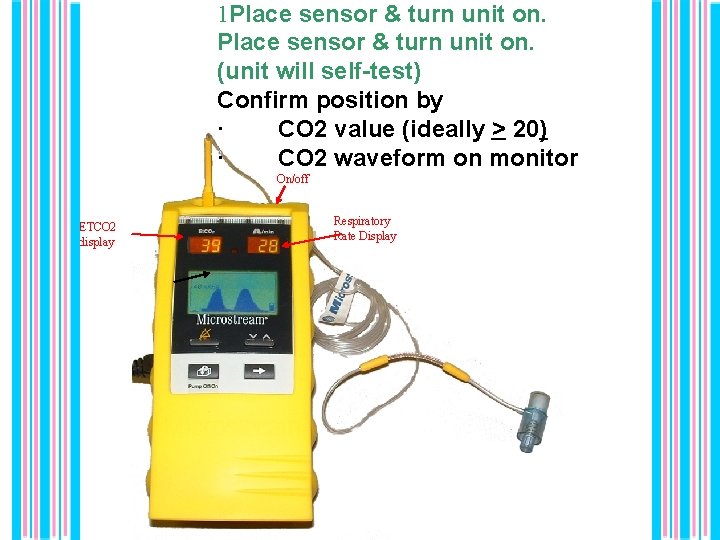

1 Place sensor & turn unit on. (unit will self-test) Confirm position by · CO 2 value (ideally > 20) · CO 2 waveform on monitor On/off ETCO 2 display Respiratory Rate Display